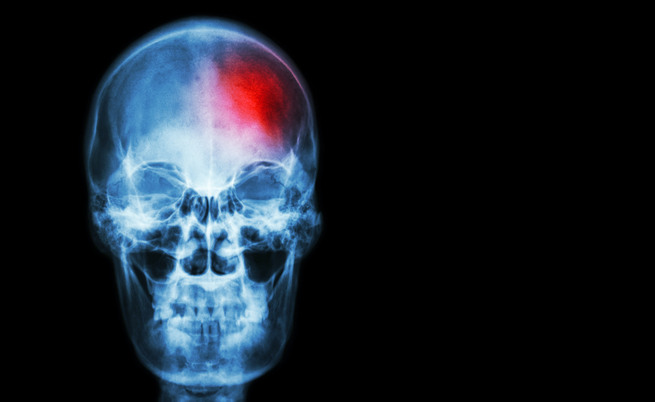

Per ictus o apoplessia cerebrale (colpo apoplettico) o stroke intendiamo una patologia vascolare cerebrale acuta. Questa può essere ischemica, dunque legata al blocco del flusso di sangue al cervello oppure emorragica, causata dalla rottura di un vaso cerebrale. L’80% degli ictus sono di natura ischemica, rappresentando la prima causa di disabilità nell’adulto e la seconda causa di mortalità e demenza nei paesi occidentali.

La patologia ischemica può essere anche transitoria e completamente reversibile. In questo caso si parla di TIA, attacco ischemico transitorio (ad esempio un embolo può essere degradato spontaneamente, permettendo nuovamente l’afflusso di ossigeno). L’ictus emorragico riconosce, come prima causa di rottura dei vasi cerebrali, l’ipertensione arteriosa. Anche l’ictus ischemico (rammollimento bianco) può trasformarsi in emorragico (infarto rosso), per la fuoriuscita di globuli rossi dai vasi cerebrali lesionati, solitamente all’interno dell’area ischemica.